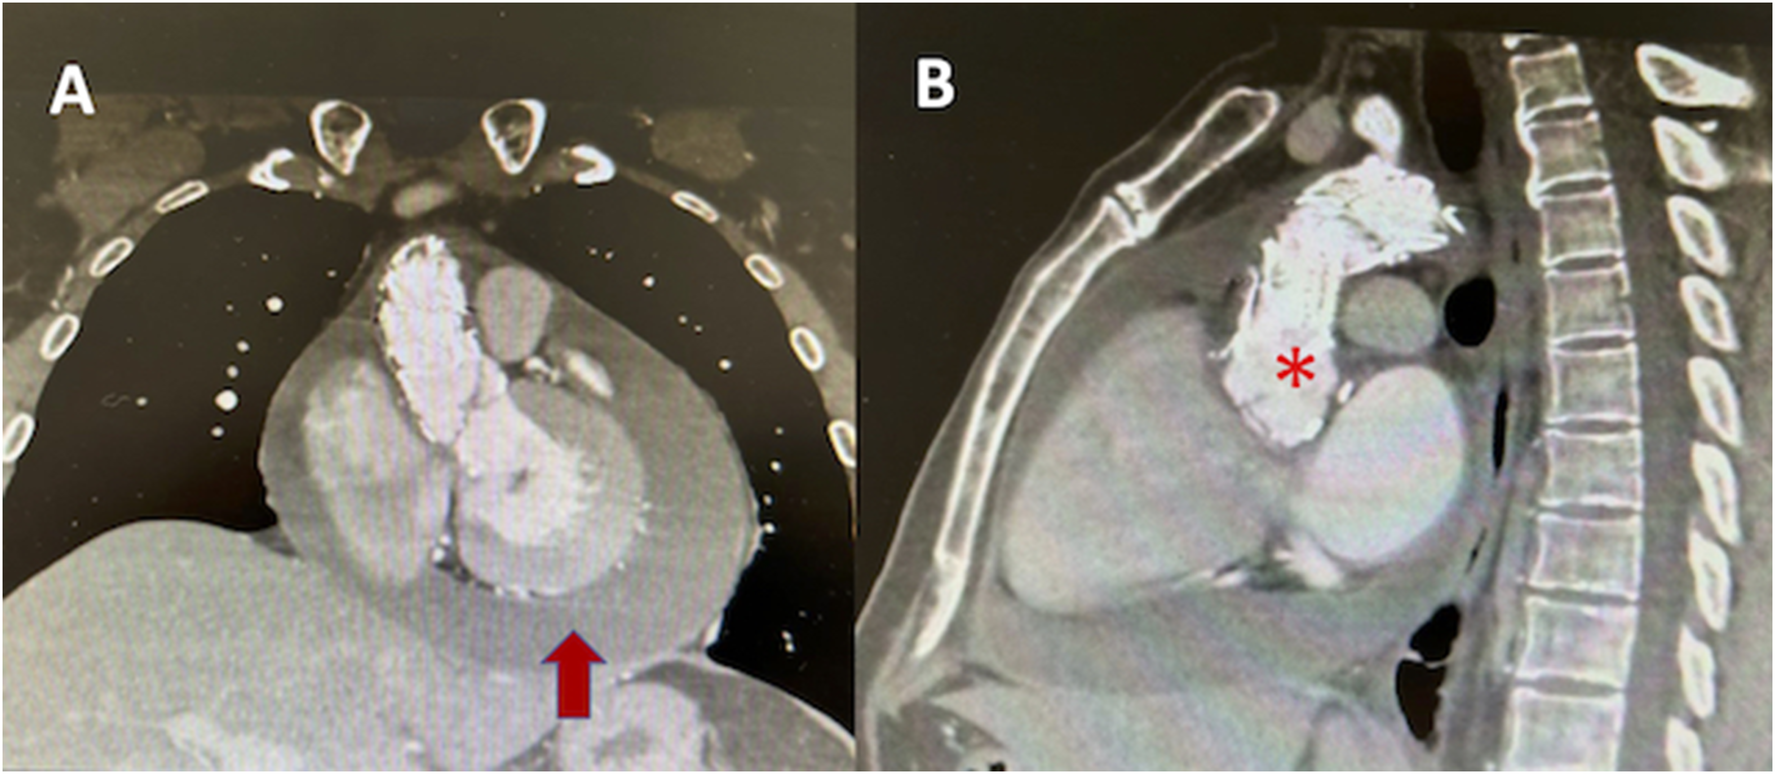

Figure 3

Angio CT of aorta (A) coronal axis showing pericardial effusion (red arrow), (B) endovascular material in ascending aorta (asterix).

Given the cardiovascular history, an aortic and great vessel's Angio CT was performed, revealing the aortic endoprosthesis in position, without leaks, dissection, or aneurysms (Figure 3). With the diagnosis of acute pericarditis and pericardial effusion, the patient was hospitalized and received oral aspirin and colchicine.

Due to the past history of aortic pathology with vascular endoprosthesis, the initial step was to rule out acute aortic syndrome (aortic dissection) or endoprosthesis complications via aortic CT, as this would require emergency surgical treatment. Initial findings suggestive of inflammation without troponin elevation or ventricular motility compromise in echocardiography led to the exclusion of myopericarditis.